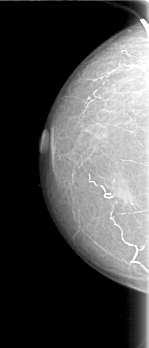

D_4072_1.LEFT_MLO

FILE: D_4072_1.LEFT_CC.OVERLAY

TOTAL_ABNORMALITIES 1

ABNORMALITY 1

LESION_TYPE MASS SHAPE IRREGULAR MARGINS OBSCURED

ASSESSMENT 0

SUBTLETY 2

PATHOLOGY BENIGN

TOTAL_OUTLINES 1

BOUNDARY